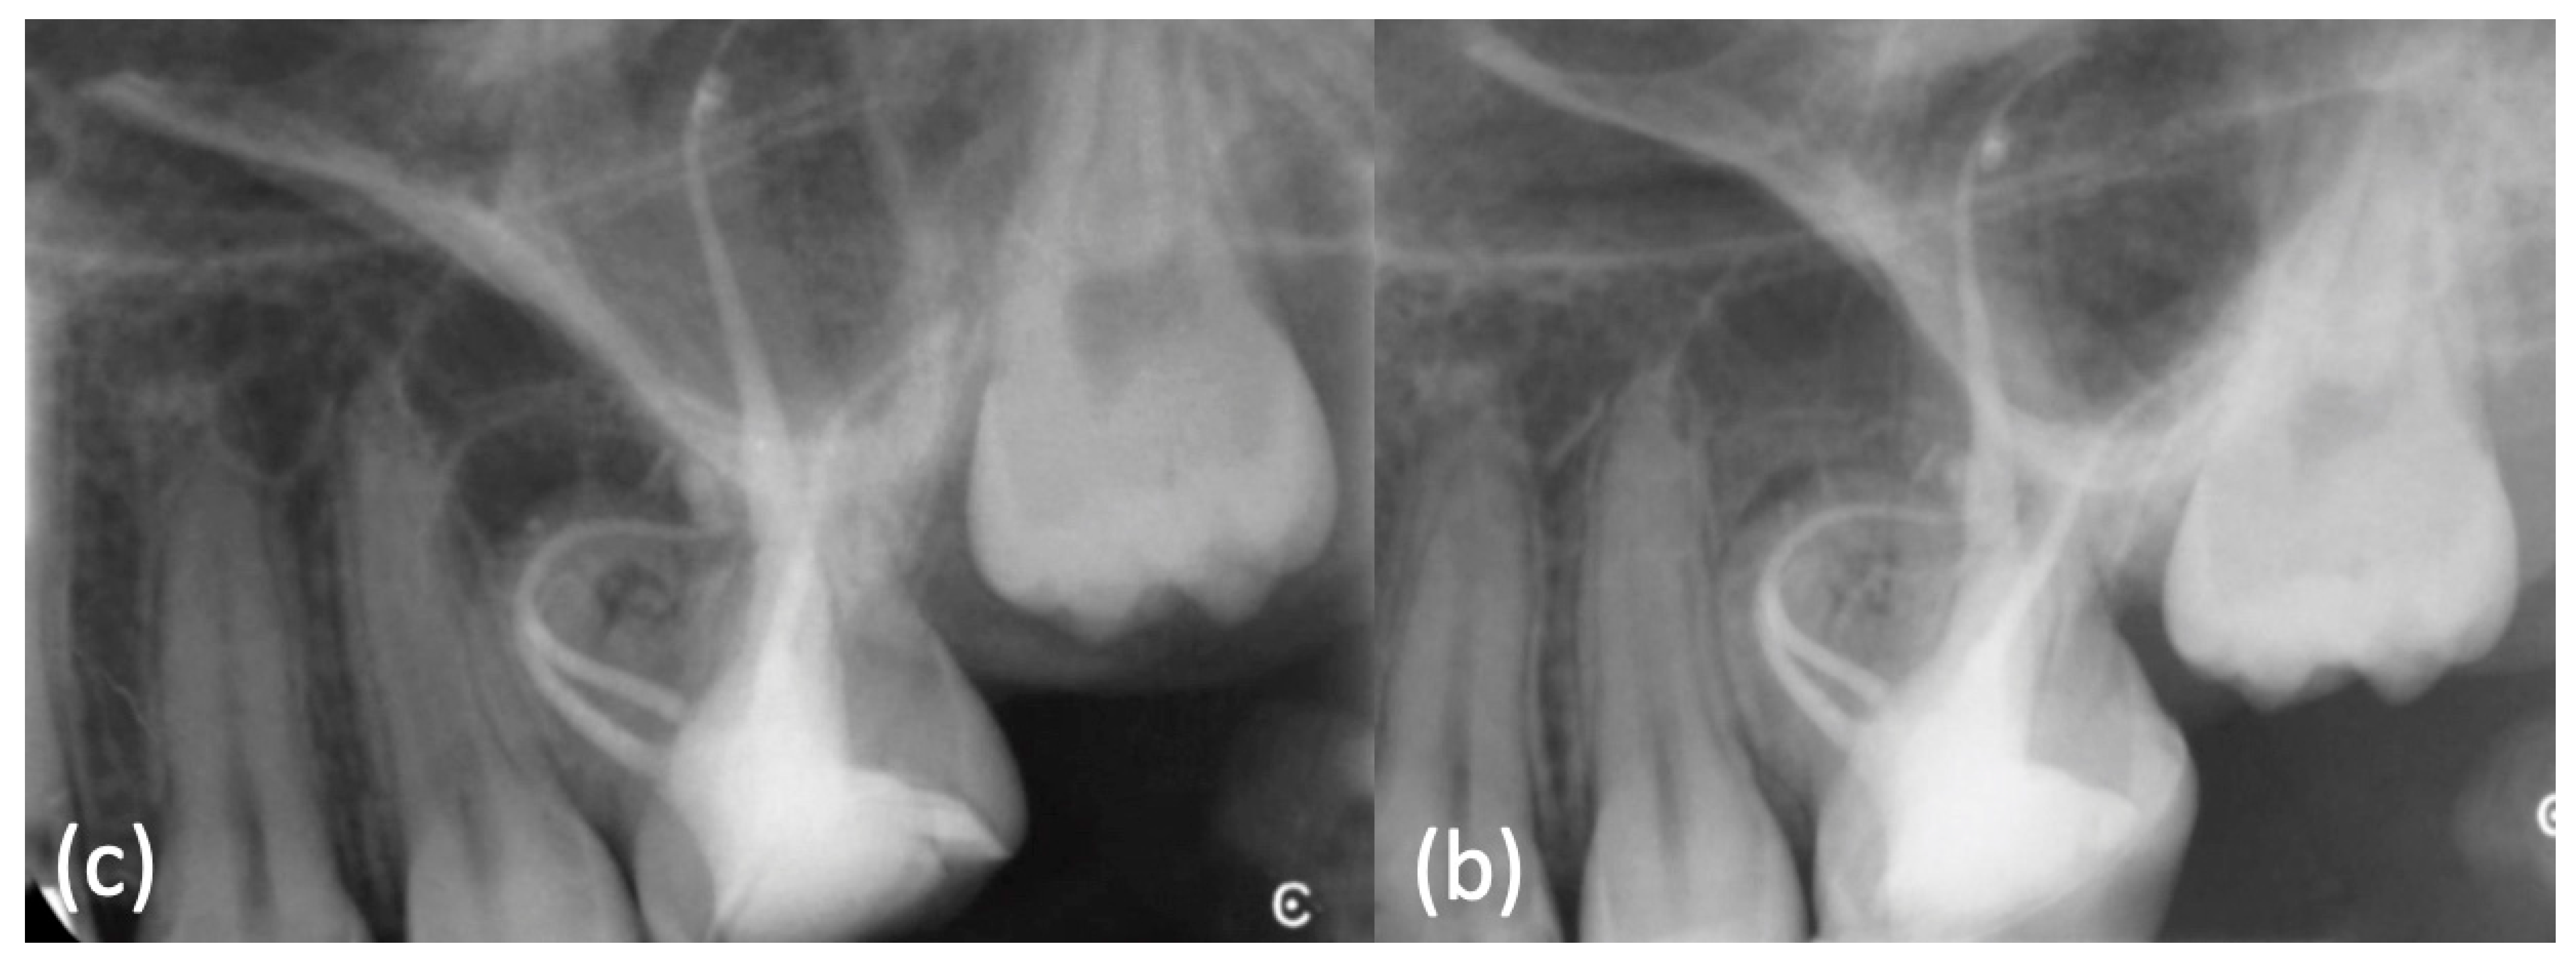

Considering the anatomical complexity, the minimal preparation and the good result obtained with the mock obturation on the 3D-model, a single cone technique with TruNatomy™ Conform Fit™ Gutta-Percha Prime 26/.04 was chosen and combined with a bioceramic sealer (EndoSequence BC Sealer HiFlow, Brasseler USA®, Savannah, GA, USA) which is flowable and can fill any irregularities or voids (Figure 8f) (Movie 10). The coronal anatomy was restored with a build-up, followed by an indirect composite overlay. A post-operative LCPA X-ray was taken (Figure 9a). Clinical and radiographic follow-up was scheduled at 6 months: the patient confirmed that the tooth had been clinically asymptomatic and periapical X-ray showed a smaller radiolucent area around the mesial buccal root (Figure 9b); closure of the existing sinus tract was observed too. The next follow-up has been planned at one year.

Figure 9.

(a) Post-operative X-ray was taken. (b) At 6 months review the periapical X-ray showed a smaller radiolucent area around the mesial buccal root.